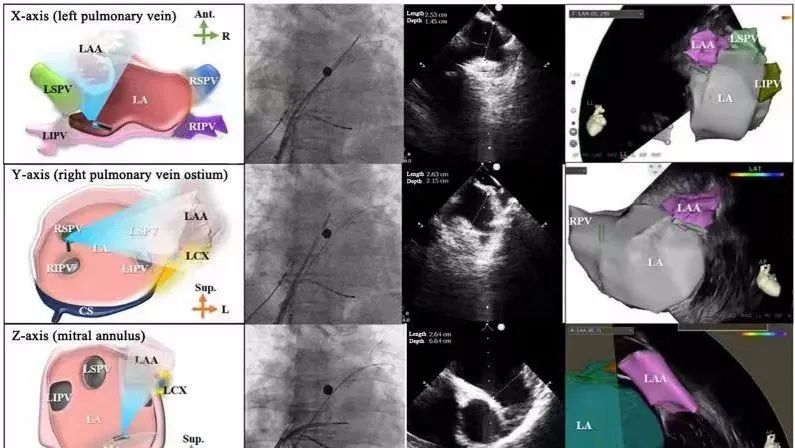

一種與心導(dǎo)管檢查相結(jié)合的超聲心動圖診斷新興技術(shù),通過將超聲探頭置于心腔內(nèi)部,發(fā)射并接收超聲信號,來精確獲取心臟解剖結(jié)構(gòu)、心臟血流動力學(xué)等信息的實時成像。與其他影像技術(shù)相比,ICE技術(shù)具有操作簡單、無輻射、安全性高、手術(shù)效率高、實用等優(yōu)勢,ICE在很大程度上有望取代經(jīng)食道超聲心動圖(TEE),成為電生理和結(jié)構(gòu)性心臟病領(lǐng)域的理想成像方式。

目前ICE技術(shù)已被應(yīng)用于左心耳封堵、房顫射頻消融、二尖瓣成形、房間隔缺損封堵等多種心臟介入手術(shù),應(yīng)用場景主要圍繞臟電生理、結(jié)構(gòu)性心臟病等領(lǐng)域,目前以電生理應(yīng)用為主。數(shù)據(jù)顯示,我國結(jié)構(gòu)性心臟病介入器械市場規(guī)模已從2017年的4億元增長至2021年的20億元,年復(fù)合增長率達48.3%;預(yù)計到2025年,該市場規(guī)模將達到104億元,可以預(yù)見ICE市場規(guī)模也將同步高速增長,未來市場發(fā)展空間廣闊。

心腔內(nèi)超聲(ICE)技術(shù)壁壘極高,國內(nèi)主要廠商核心部件仍舊為進口,集成了超聲和圖像處理最前端技術(shù),包括超聲探頭、線纜、軟件成像算法等,是當(dāng)前內(nèi)窺超聲方向最具挑戰(zhàn)的領(lǐng)域。ICE的應(yīng)用經(jīng)歷了2D平面成像、3D三維立體成像、以及4D的實時三維立體成像階段。